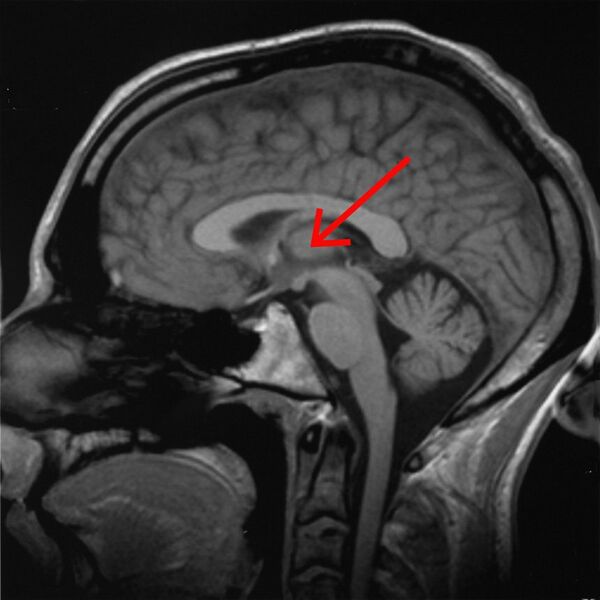

Таламус расположен вблизи центра мозга и входит в число структур таламической области промежуточного мозга. Он залегает под структурами большого мозга, но возвышается над структурами среднего мозга. Восходящие аксоны, исходящие из нейронов ядер таламуса, формируют пучки миелинизированных нервных волокон. Эти пучки нервных волокон обильно проецируются на различные области коры больших полушарий головного мозга во всех направлениях. Медиальная поверхность обеих половинок таламуса одновременно является верхней частью боковой стенки третьего желудочка головного мозга. Она соединена с соответствующей медиальной поверхностью противоположной половинки таламуса плоской полосой белого вещества. Эта полоса представляет собой пучок миелинизированных нервных волокон и называется межталамическим сращением, или промежуточной массой третьего желудочка, или срединной комиссурой (срединной спайкой) таламуса.

Наконец, последняя группа ядер таламуса, так называемые медиальные ядра, или «ядра средней линии», покрывает собой часть медиальной поверхности обеих половинок таламуса, и примыкает к верхней боковой стенке третьего желудочка головного мозга. Эти ядра средней линии (медиальные ядра) каждой из половинок таламуса могут соединяться между собой тонким и плоским серым пучком нервных волокон, так называемым межталамическим сращением. Выраженность межталамического сращения вариабельна не только у разных видов позвоночных, но даже у разных особей одного и того же вида (в том числе у разных людей), вплоть до её полного отсутствия. Отсутствие или слабая выраженность межталамического сращения практически не влияет на функциональность таламуса и является не патологией, а лишь анатомической особенностью (такой же, как наличие артерии Першерона)[8].

У некоторых людей имеется так называемая «артерия Першерона» — редкая анатомическая вариация, при которой от одной из двух задних мозговых артерий, левой или правой, отходит единственная парамедианная таламическая артерия, кровоснабжающая парамедианные части обеих половинок таламуса. Обычно же от левой задней мозговой артерии отходит артерия, кровоснабжающая парамедианную часть левой половинки таламуса, а от правой — аналогичная артерия, кровоснабжающая парамедианную часть правой половинки[24][22].

Однако таламическим синдромом в настоящее время нередко называют не только синдром таламической боли, как в исходном определении Дежерина и Русси, но любые клинические синдромы, связанные с поражением таламуса. Так, в частности, одно- или, чаще, двусторонняя ишемия области, кровоснабжаемой парамедианной артерией, может вызвать серьёзные проблемы с регуляцией двигательных, глазодвигательных и речевых функций, вплоть до развития атаксии или акинетического мутизма (немоты и неподвижности), или паралича взора[62]. Таламокортикальная дизритмия может вызывать нарушения цикла сна и бодрствования, а также разнообразные другие нарушения, в зависимости от характера затронутых дизритмией таламокортикальных цепей[63]. Окклюзия артерии Першерона может привести к двустороннему инфаркту таламуса[64].